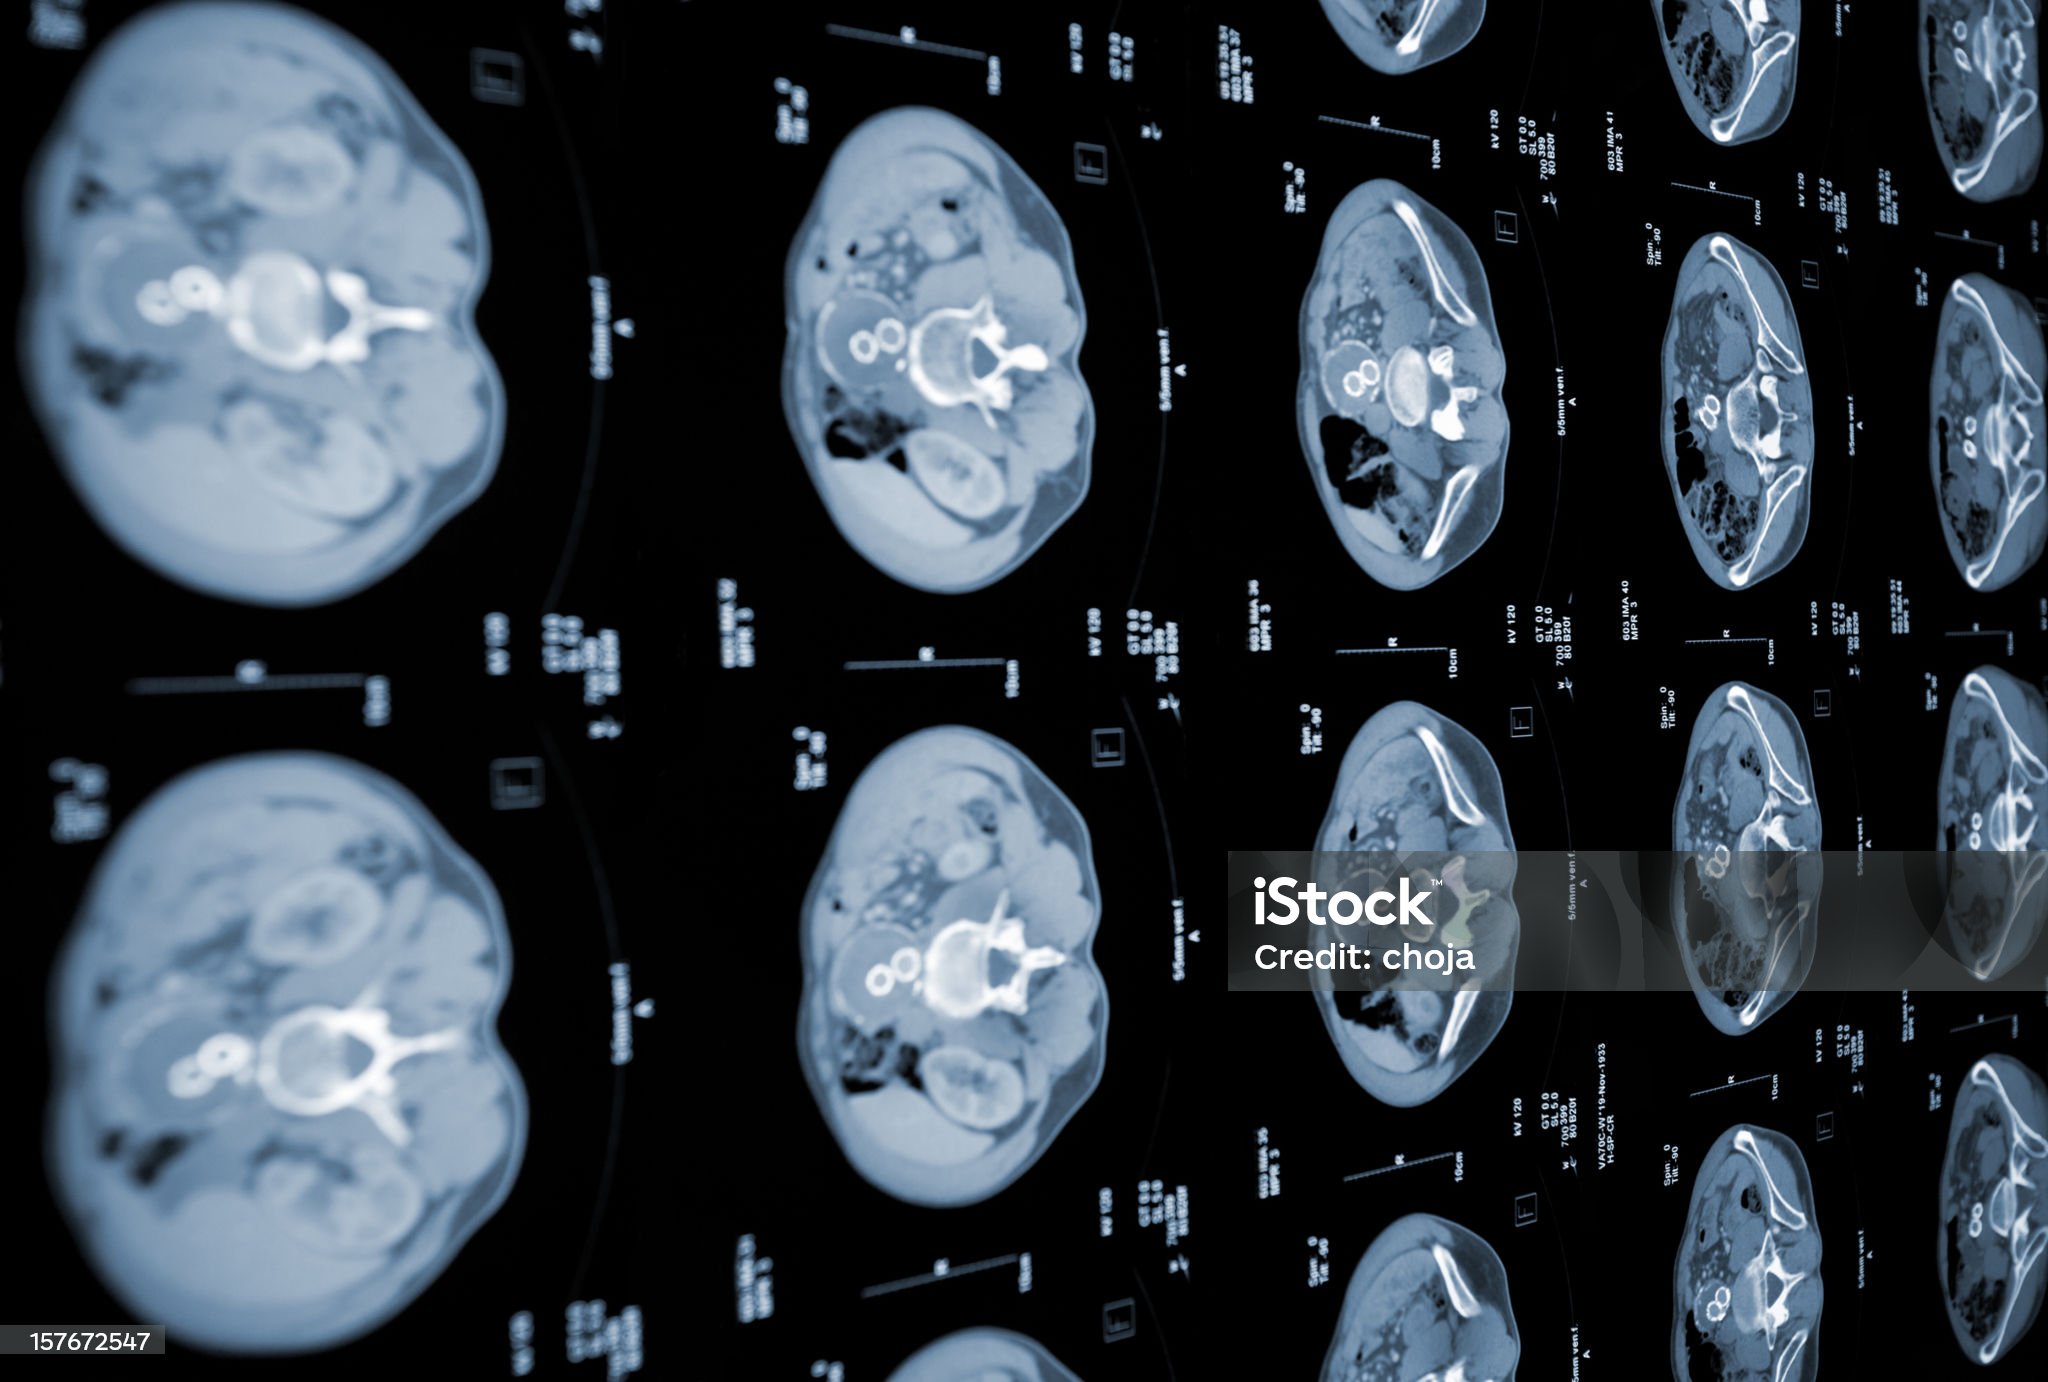

뇌출혈은 한 번 발생하면 회복이 어렵고 후유증이 남을 가능성이 높기 때문에 사전 예방이 매우 중요합니다. 예방을 위해서는 먼저 고혈압 관리가 필수입니다. 정기적으로 혈압을 측정하고, 이상이 있을 경우 즉시 병원 진료를 받아야 하며, 필요 시 약물 치료를 꾸준히 이어가는 것이 중요합니다. 나트륨 섭취를 줄이고, 싱겁게 먹는 습관을 들이며, 규칙적인 운동을 통해 혈압을 안정적으로 유지해야 합니다. 흡연과 음주는 혈관 건강에 매우 해롭습니다. 흡연은 혈관을 수축시키고 내벽을 손상시키며, 음주는 혈압을 상승시키고 심장에 부담을 줍니다. 따라서 금연과 절주는 뇌출혈 예방을 위한 필수 생활습관입니다. 특히 중년 이상 남성의 경우 흡연과 음주 습관이 동시에 있는 경우 위험도가 더욱 상승하므로 주의가 필요합니다. 스트레스 또한 혈압을 급격히 상승시키는 원인이 되므로, 평소 스트레스를 해소할 수 있는 방법을 찾는 것이 중요합니다. 명상, 요가, 산책, 독서 등은 정서적 안정을 도울 수 있으며, 충분한 수면 역시 뇌 건강 유지에 필수적입니다. 이 외에도 규칙적인 건강검진을 통해 뇌동맥류, 동정맥 기형, 혈관기형 등을 조기에 발견하는 것이 중요합니다. 고위험군은 정기적인 MRI나 CT 검사를 통해 위험 요소를 사전에 파악해야 합니다. 특히 가족력이 있는 경우, 선제적으로 검사를 받고 관리계획을 세우는 것이 바람직합니다. 비만, 고지혈증, 당뇨 등 대사 질환의 관리는 뇌출혈뿐만 아니라 뇌경색, 심근경색 등 다른 혈관질환의 예방에도 도움이 됩니다. 식습관을 개선하고, 트랜스지방과 포화지방의 섭취를 줄이며, 충분한 섬유소와 미네랄이 포함된 식단을 구성해야 합니다. 이처럼 일상에서 실천 가능한 습관 개선이 바로 뇌출혈 예방의 첫걸음이 됩니다.